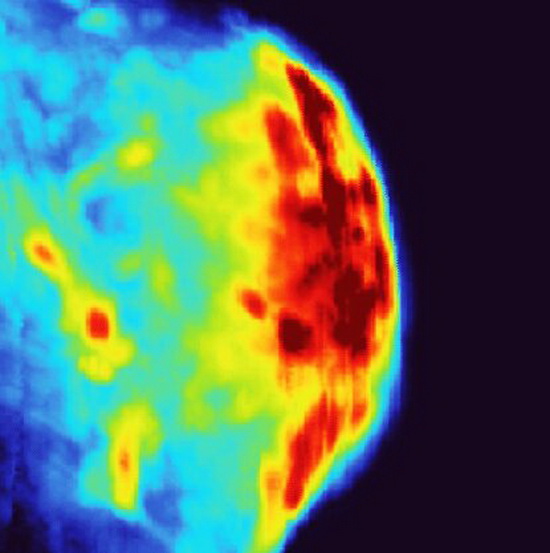

Màu đỏ trên hình ảnh quang âm cho thấy vị trí các hạt nano vàng tích tụ trong khối u bàng quang. Ảnh: Science Advances (2025)

Canning đã nghe nói về công nghệ của nhà nghiên cứu này và tò mò liệu việc kết hợp công nghệ ấy với các nano có hình ngôi sao của anh sẽ đem lại kết quả như thế nào. Nhà nghiên cứu người Việt cũng có sự tò mò tương tự. Trong các thí nghiệm ban đầu, nhóm nghiên cứu nhận thấy hệ thống hình ảnh của Vũ Trí có thể dễ dàng theo dõi sự tích tụ các nano của Canning trong các khối u và mô mục tiêu trên khắp cơ thể động vật.

Khi kết hợp với hệ thống PACT của Vũ Trí, nhóm nghiên cứu có thể dễ dàng phát hiện và chụp ảnh các hạt nano, đồng thời theo dõi tiến trình xử lý quang nhiệt. Nhờ vào việc theo dõi nhiệt độ chính xác hơn, nhóm nghiên cứu có thể xác định được liều lượng nhiệt độ lý tưởng cần thiết để kích hoạt các hạt nano và tiêu diệt tế bào.